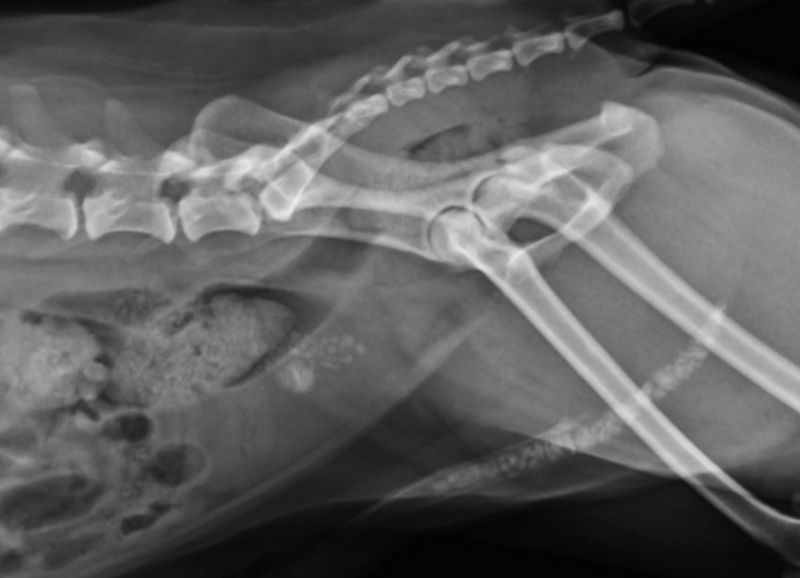

血尿、頻尿、滴尿?竟是膀胱結石作怪! 9 歲公狐狸犬 財財 血尿近一年,近期更出現頻尿、滴尿等症狀。經 X 光檢查 發現 膀胱與尿道佈滿結石,甚至完全阻塞尿道!手術中成功將結石沖回膀胱並切開取出,但尿道黏膜受損,需放置導尿管協助修復。經住院觀察,財財順利拔除導尿管出院,恢復排尿順暢,擺脫結石困擾!